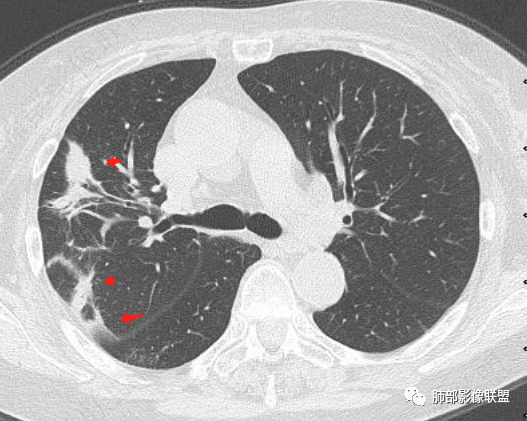

放射小白: 晨读病例:女性,70岁,风湿性多肌痛病史,右肺见不规则结节,边缘及周围见纤维索条影,考虑OP,药物性肺损伤。

谢加平: 右肺上叶外周,近胸膜下结节病灶,侧向融合,边缘清,见平直边,与胸膜平行分布,支气管进入略扩张,周围见多发长索条影,方向肉芽肿性炎症,建议隐球菌荚膜抗原检查,肿瘤不支持,经皮肺穿刺病理检查!

红日初升: 胸膜下结块,平行胸膜,收缩力较强,肉芽肿样边缘,考虑炎性,小卫星灶、似有凝固性坏死,隐球>op

小兜: 晨读,女,70岁,风湿性多肌痛病史一年,半月前体检发现肺部阴影,无症状,口服药物治疗。现片示:右肺胸膜下条形实变影,局部层面似见多结节融合,周边伴条索影。下方近叶间胸膜处斑片状实变影伴条索影,宽基底与胸膜相连。综合考虑为炎性病变,隐球菌或OP可能

宇宙: 右肺上叶胸膜下结节,多结节融合,长轴平行胸膜,边缘模糊,周围长索条,胸膜牵拉,近端支气管充气扩张,考虑隐球菌,鉴别OP

看图说话: 右肺上叶外胸膜下结节,边缘清,密度均匀,边缘长索条,支气管壁增厚,进入略扩张,胸膜牵拉,考虑机化性肺炎,隐球。

玫: 晨读:右肺上叶胸膜下软组织密度影,边缘模糊,周围见条索影及少许磨玻璃影,轻度胸膜牵拉,考虑炎性病变。

金豆 (刘权威): 右肺上叶胸膜下团块,支气管充气征,边缘纤维索条,磨玻璃,OP。

黄棘: 右肺上叶近胸膜下病灶,多个融合,边缘清,与胸膜平行分布,支气管进入后堵塞,周围见多发长索条影,考虑隐球菌

果哣.: 右肺上叶靠近胸膜结节影,平直为主,边缘清晰,支气管进入后截断,有扩张,考虑炎性隐球菌可能

丽: 晨读,老年女性,右肺上叶不规则病灶,边缘多发长索条,支气管穿行达病灶远端,常规抗炎无明显吸收,考虑炎性病变,隐球菌可能大

衡妈: 老年女性,右肺上叶沿胸膜下不规则实性病灶,长轴平行于胸膜,有结节融合感,边缘部分彭隆部分平直,周围可见数条纤维灶影,病灶内可见充气支气管征未达远端,首诊考虑慢性炎性肉芽肿,隐球菌?机化性肺炎?建议增强扫描及ct下穿刺活检。

放射线 (王秀仙): 右肺上叶胸膜下结节样影,边缘平直收缩,胸膜牵拉,支气管进入病灶并扩张,部分支气管进入后阻塞,长轴平行于胸膜,周围可见片状及条索状影,隐球?机化性肺炎?

张延军: 病变与胸膜平行,近端见气管进入,口服激素治疗史 考虑隐球菌感染 伴OP样改变

晨读:女,70,未诉症状。风湿性多肌痛病史,口服强的松等药物治疗。胸部CT:右肺上叶多发不规则斑片影,沿支气管分布,部分病灶侧向融合、平行于胸膜,边缘平直内收为主、部分彭隆,周围模糊晕、可见数条纤维灶影,胸膜牵拉,病灶内可见充气支气管征、管腔不畅,考虑慢性炎症,PC?OP?鉴别腺Ca、SCLC等。

瑞欣 (刑瑞欣): 晨读,老年女性,右肺上叶不规则高密度影,可见胸膜牵拉,边缘光滑平直,与胸膜平行,周围条状影,可见支气管充气征,有风湿病史,考虑机化性炎症,鉴别隐球菌,腺癌

良孑: 右肺胸膜下多发结节,长轴与胸膜平行,部分病灶有多结节融合,可见近端支气管充气征,有晕征及晕中软毛刺,长期口服激素病史,抗炎效果欠佳。病灶形态单一,无播散性树芽,结节内无支气管穿行,单侧发病,收缩力差,可排除TB,OP及淋巴瘤,综和考虑支持隐球菌

尘缘: 典型的隐球机化期改变